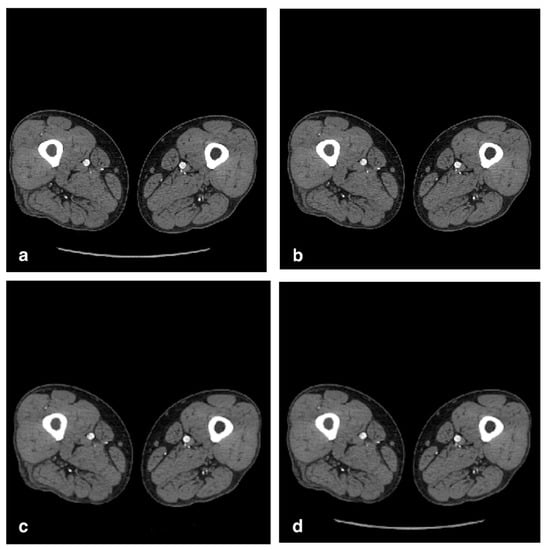

2. Materials and Methods